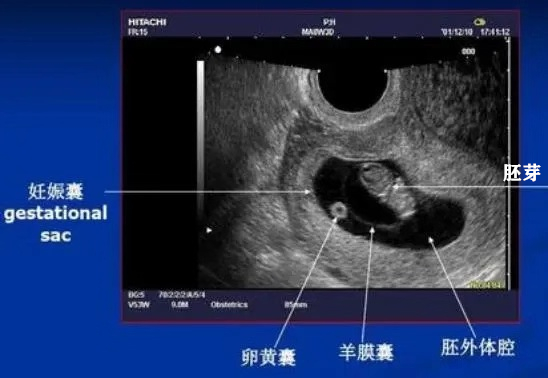

发生胎停后,孕妈的早孕反应消失,做超声检查可能表现为空孕囊、有胎芽却没有胎心、或者孕囊变形等。

孕5周后做经阴超声检查,会发现宫腔内有孕囊,孕囊里有胎芽和卵黄囊,胎芽上可以看到胎心搏动,经过超声检查可以判断是否有胚胎停育。

一般情况下,孕5周可见孕囊,5-7周时,孕囊的平均直径生长速度是1mm/天。孕6周以后可以看到胎心搏动,以及1-2mm的胎芽,7周前胎芽的生长速度为1mm/天,孕早期结束胎芽可达80mm。